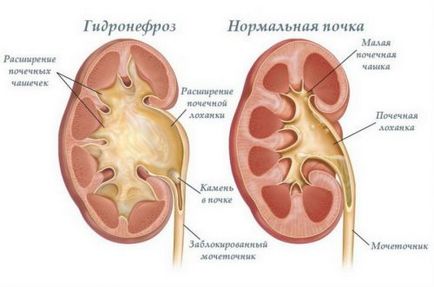

Раздвоения бъбрек се увеличи значително. Ако непълно разделяне CHLS цяло остава в пълна - се трансформира в две независими системи с индивидуални уретери - основна и разширение. В последната може самостоятелно растат в кухината на пикочния мехур или свързване с основната преди да влезе в балона. Ако двата уретера се сливат, на мястото на тяхната връзка се образува стеснение, че може да прекъсне потока на процеса на урина и обратната му актьорски състав в таза. Такава протичане на заболяването може да бъде най-хидронефроза - разширение чаши и таза - и последваща атрофия на бъбречната паренхим.

В случай на остра хидронефроза хирургична интервенция е необходимо, и с пълното развитие на бъбречна недостатъчност - неговото отстраняване.

бъбрек хидронефроза - заплашително усложнение на удвоила